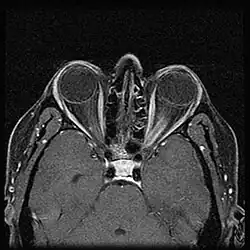

Obrazowanie rezonansu magnetycznego jest złotym standardem w diagnostyce ONSM[5]. Tomografia komputerowa może uwidocznić guz nerwu, ale tylko MRI, szczególnie z kontrastem gadolinowym, pozwala prześledzić przebieg nerwu w kanale wzrokowym. Postępy w technikach obrazowych pozwoliły na stawianie rozpoznania na ich podstawie w połączeniu z obrazem klinicznym, tym samym oddalając konieczność biopsji guza.